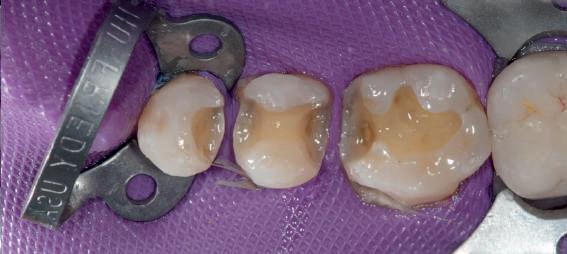

HYBRID COMBINATION RESTAURATIONS

Vonlay-uri: o alternativă conservatoare estetică la coroanele cu acoperire totală